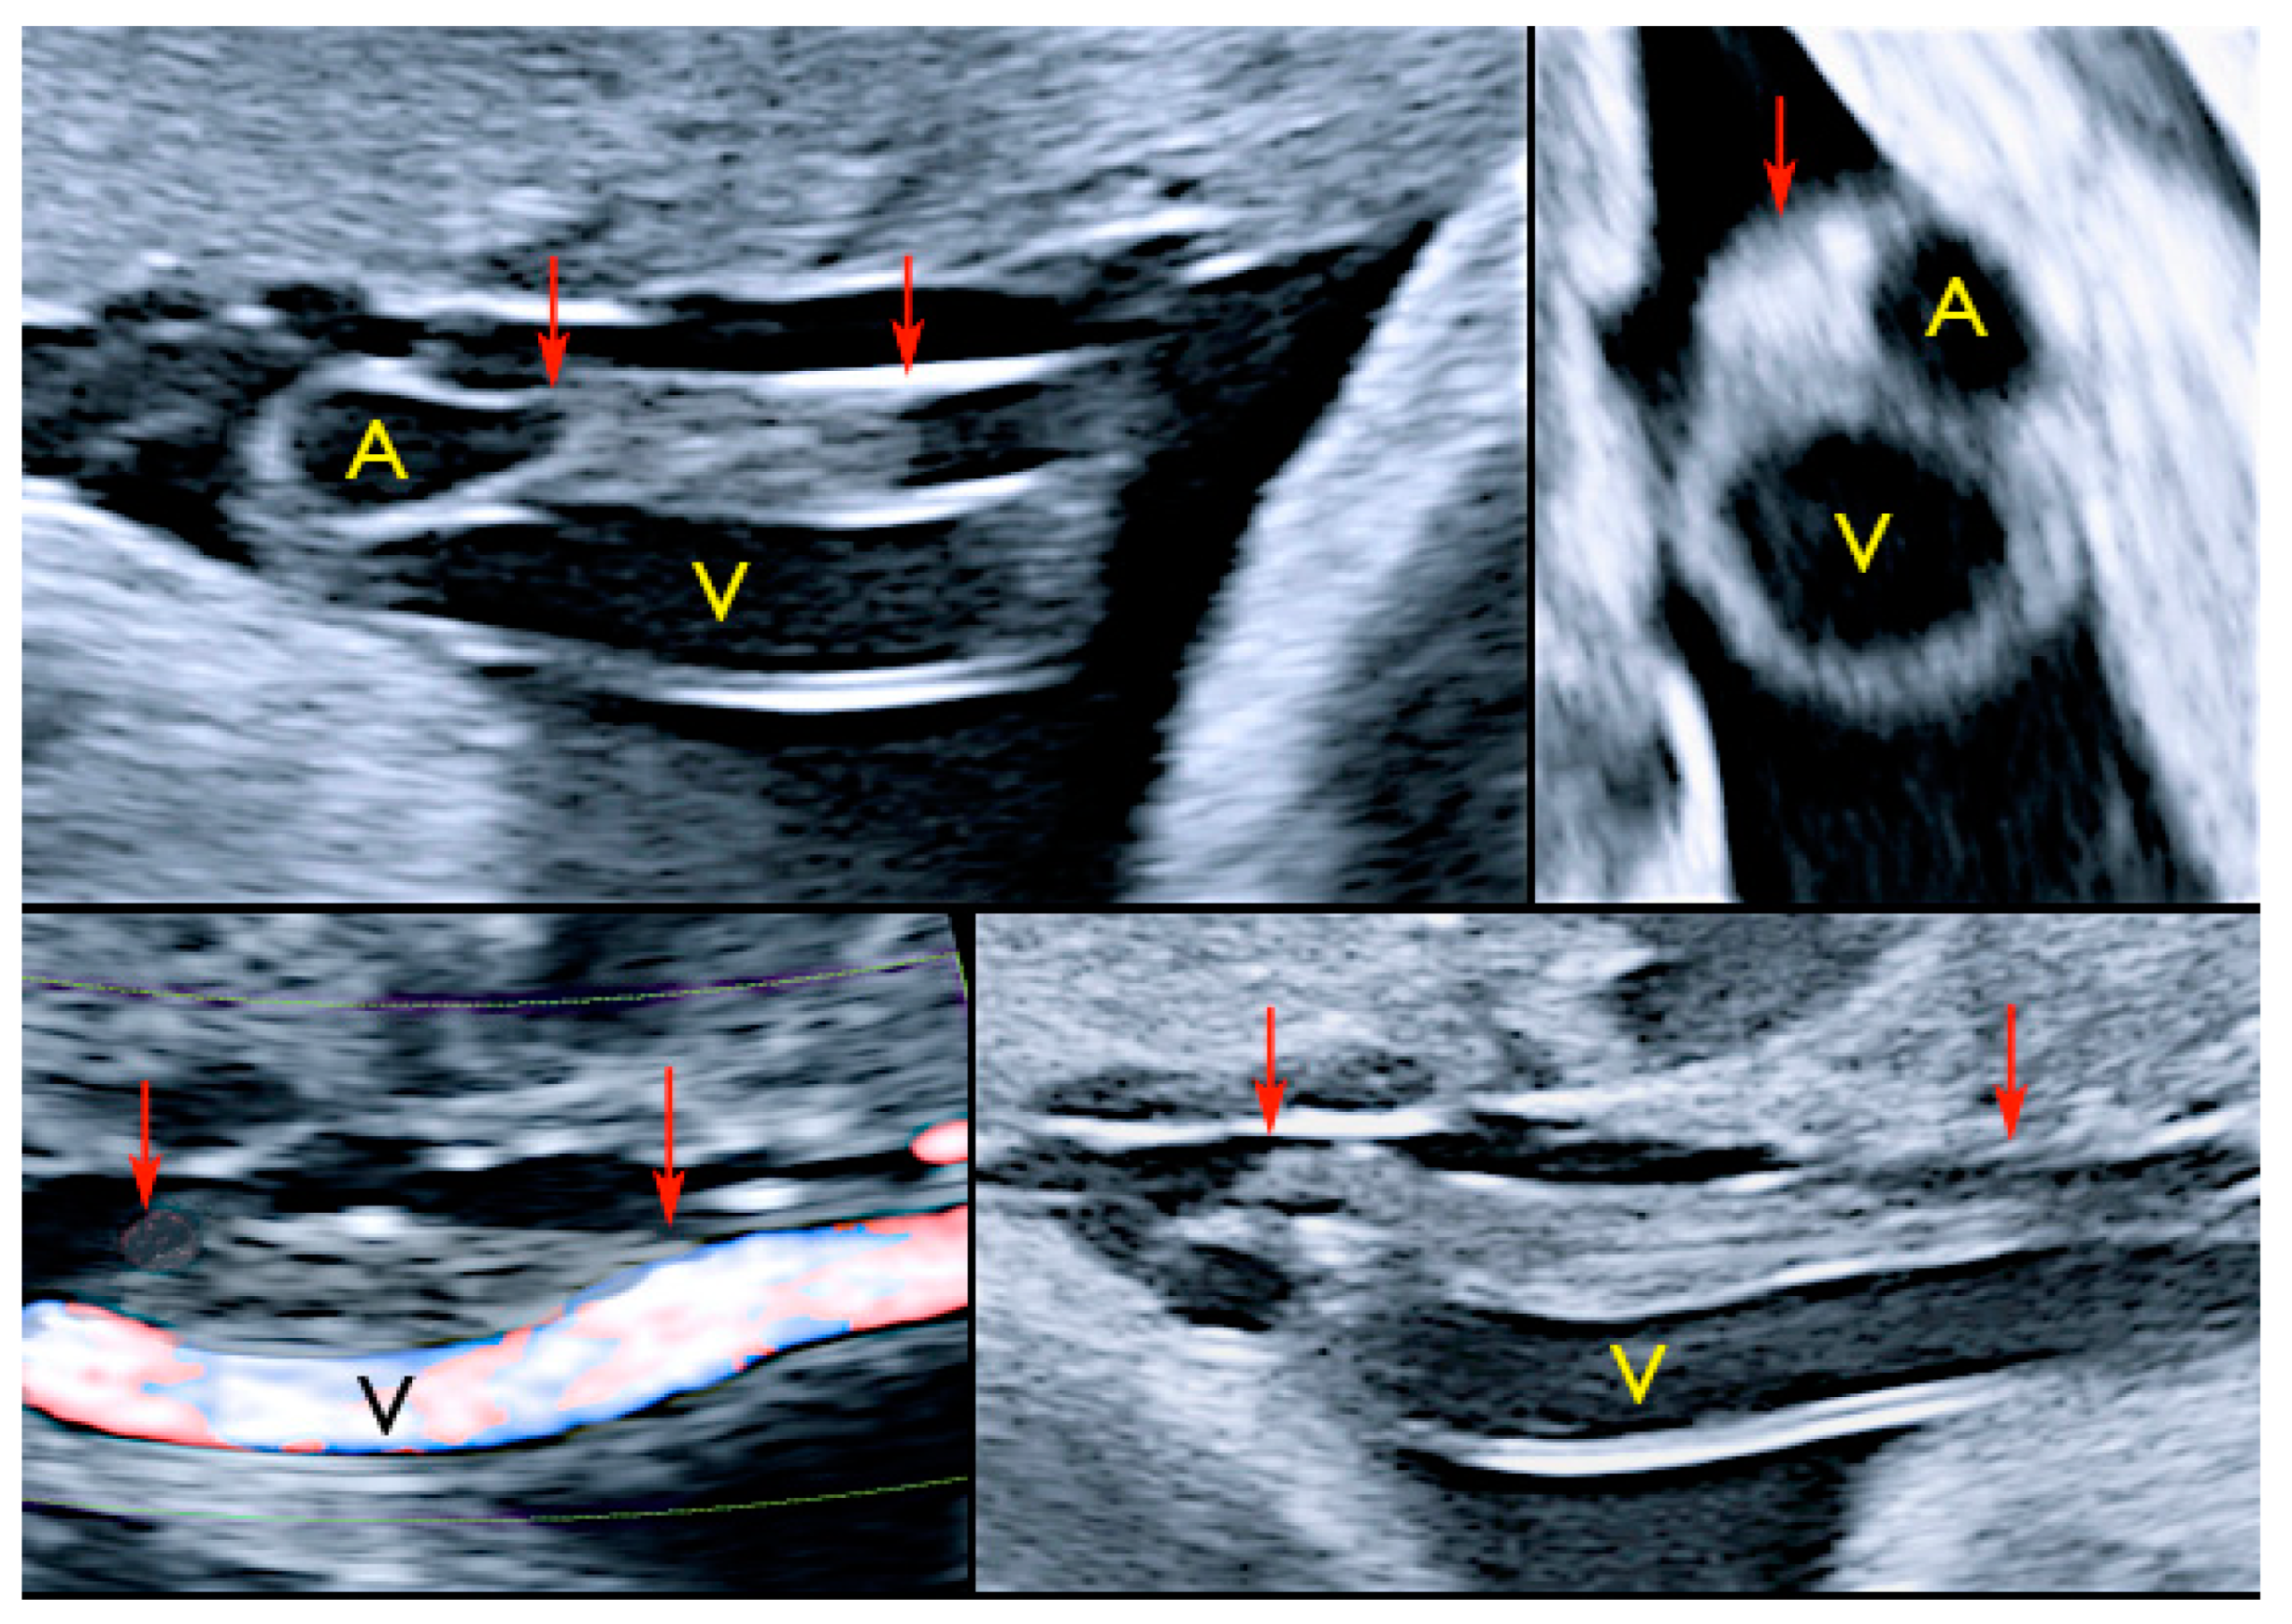

3.2.12. Umbilical Vessel Thrombosis

Risk factors for umbilical vessel thrombosis include the hypercoiling of the umbilical cord and deficient Wharton’s jelly [69]. Umbilical artery thrombosis is a rare event and is associated with intrauterine growth restriction, fetal organ infarcts and stillbirth [69]. Umbilical vein thrombosis is also a rare event and is associated with worse perinatal outcomes when compared to umbilical artery thrombosis, as there is only one vein in the umbilical cord to deliver oxygenated blood from the mother to the fetus [69]. Generally, the diagnosis is made after birth, but sonographic diagnosis is possible by visualizing an echogenic core representing the thrombus, associated with turbulent flow on color Doppler with a dilated umbilical segment, when the vein is not completely occluded, or by not finding two blood flows within the umbilical arteries [69] (Figure 33).

Figure 33.

Pregnancy at 32, 34 and 35 week’s gestation. Two-dimensional ultrasound in longitudinal and axial scan of the umbilical cord. A moderate echogenicity corresponds to segmental thrombosis of an umbilical artery. The thrombosis zone is indicated by red arrows and the progressive extension is further delimited by arrows (Legend: A: umbilical artery; V: umbilical vein).